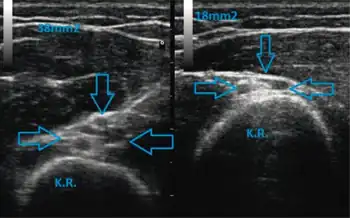

There are several mechanisms of nerve injury including mechanical lesions, ischemia, immunologic attack, metabolic disorder, toxic agents, and exposure to radiation.[6] The most common mechanism of injury is nerve compression in which external pressure causes decreased blood flow to the nerve and deformation of the nerve fibers.[6] Repeated or prolonged compression of the nerve results in ischemia and ultimately edema above and below the source of the pressure (I). The thinning of myelin sheaths or focal demyelination are the main consequences of the injury that lead to conduction blockage.[6]